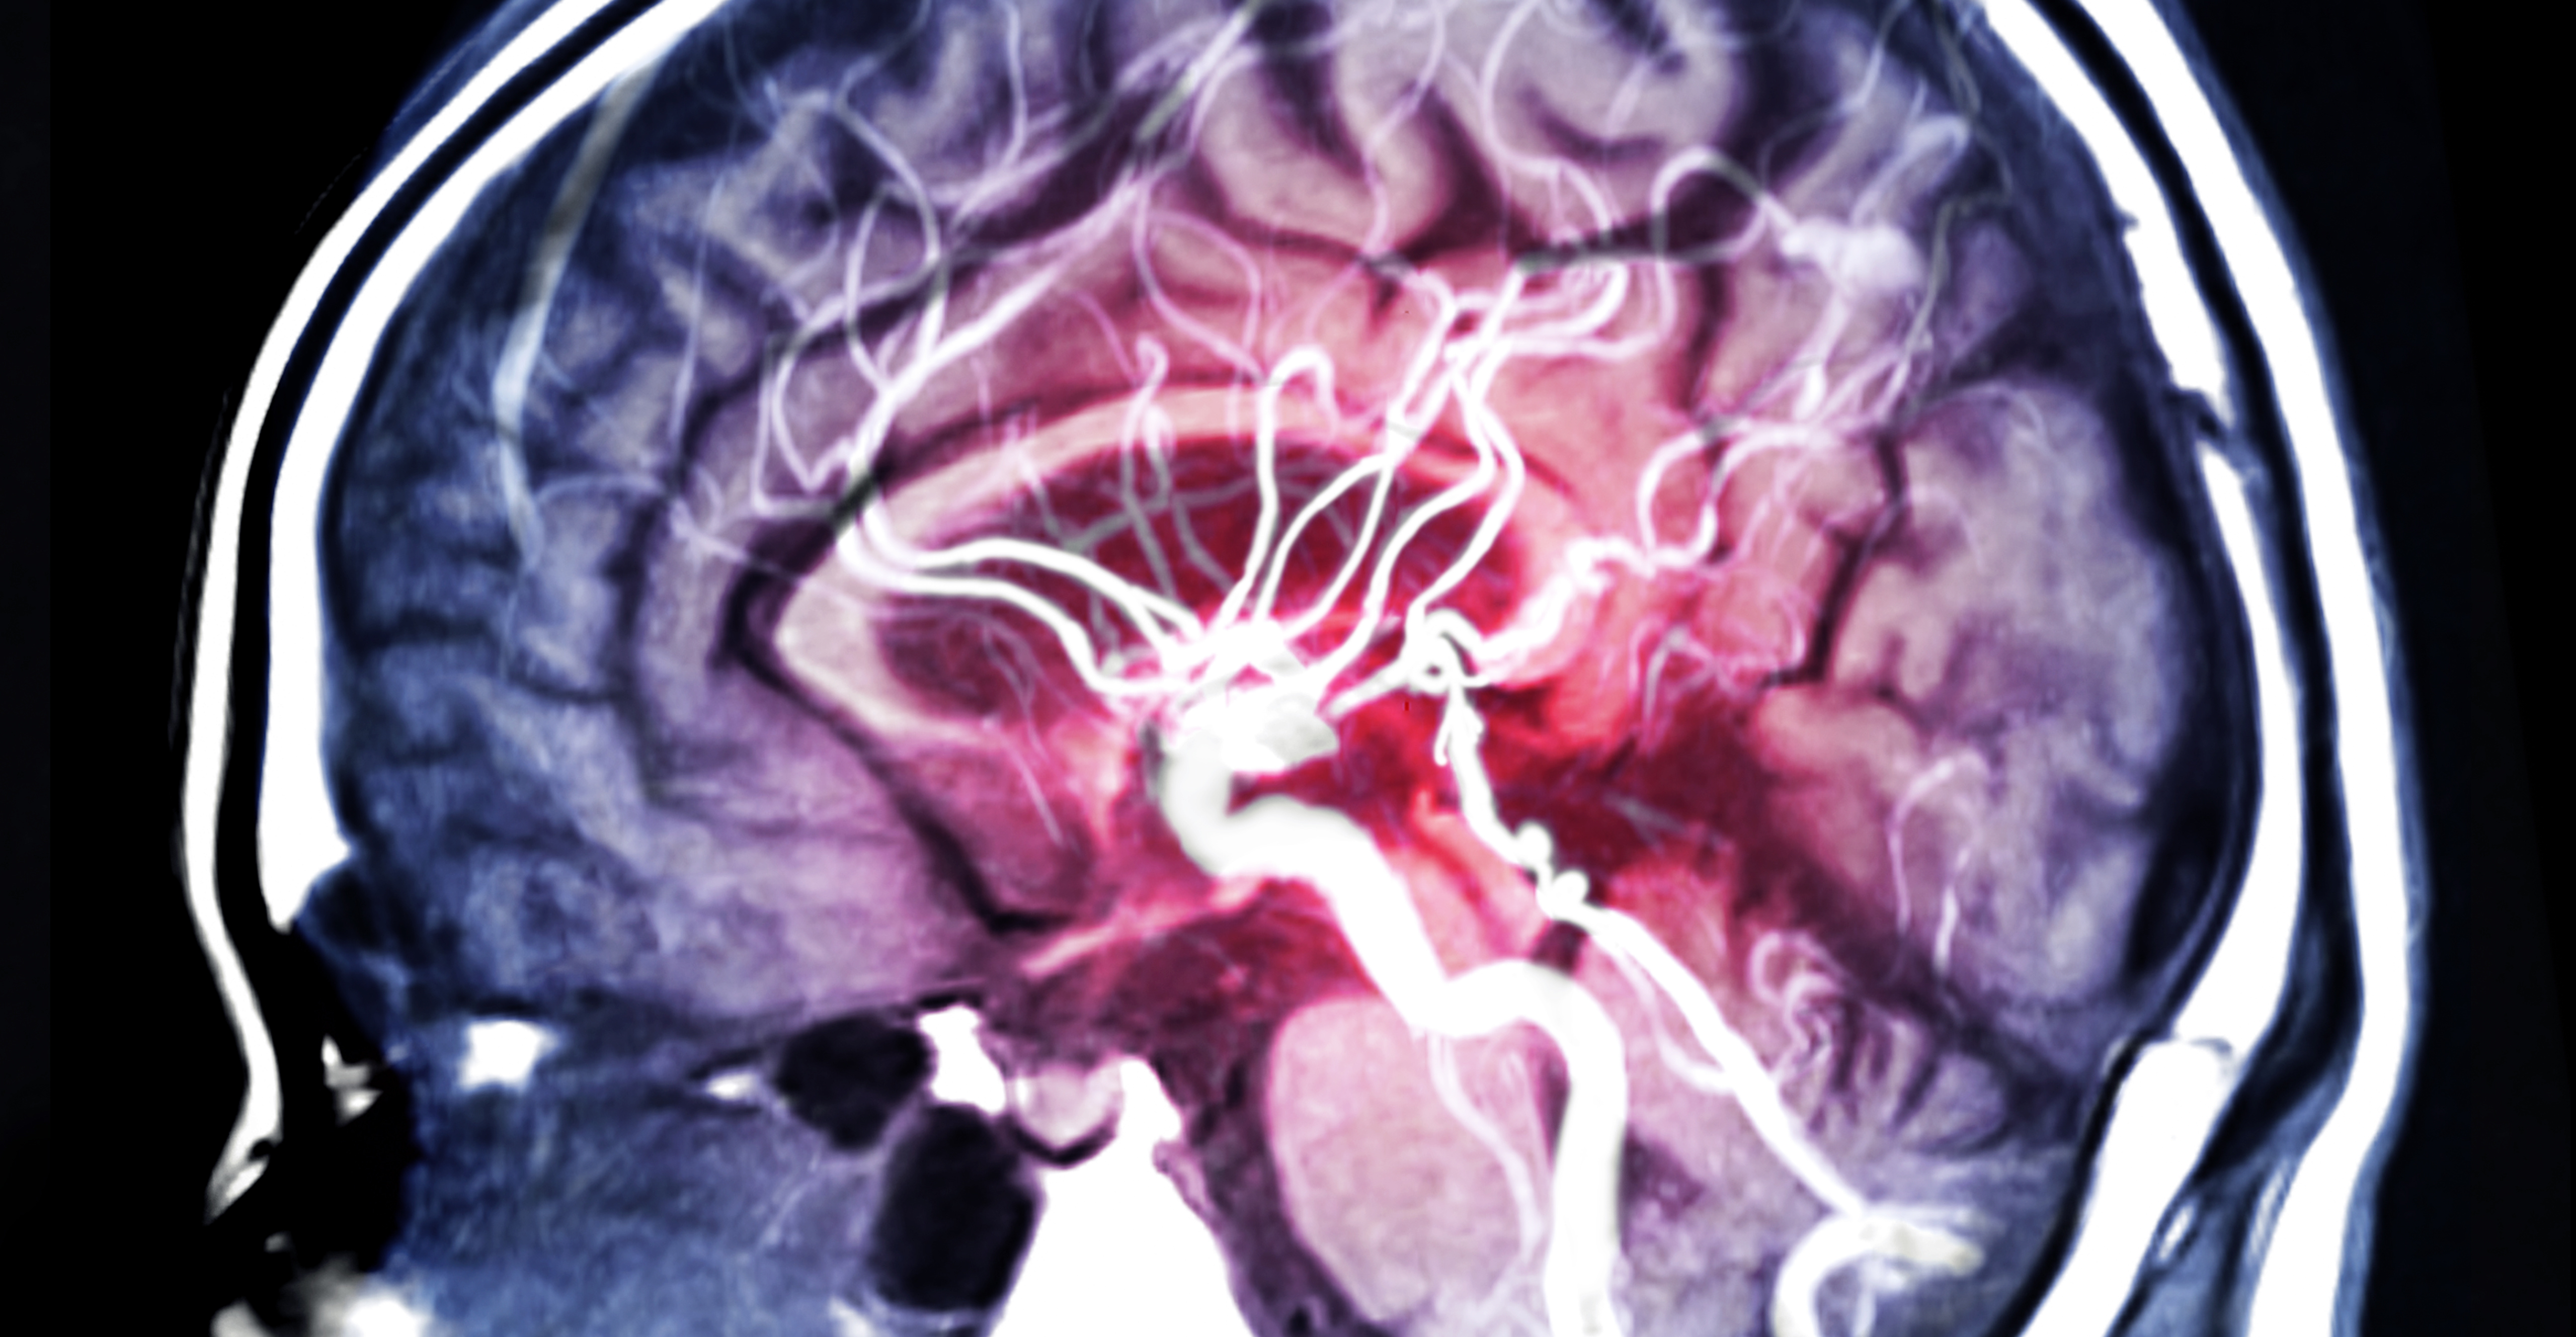

Vers un nouveau mode de prise en charge de l'AVC ? Les images du cerveau des patients montrent que la taille des dommages de l'AVC est considérablement réduite avec le nérinétide.